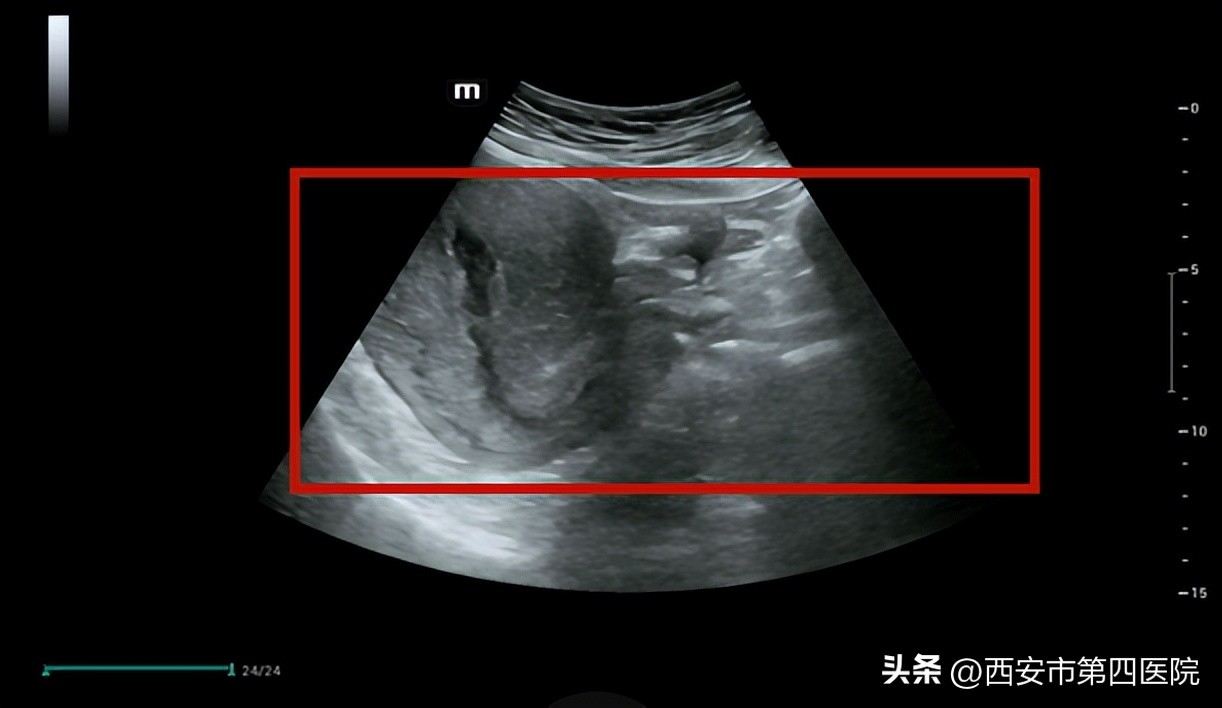

医生建议进行B超检查,提示“膀胱残余尿879ml”,根据情况这属于典型产后尿潴留。

(上图红框部分为膀胱被尿液充盈暗区,下图红框为排尿后暗区消失)

3次治疗后排尿功能恢复正常,B超显示无残余尿 。李女士感慨:“终于不用插导尿管了!”